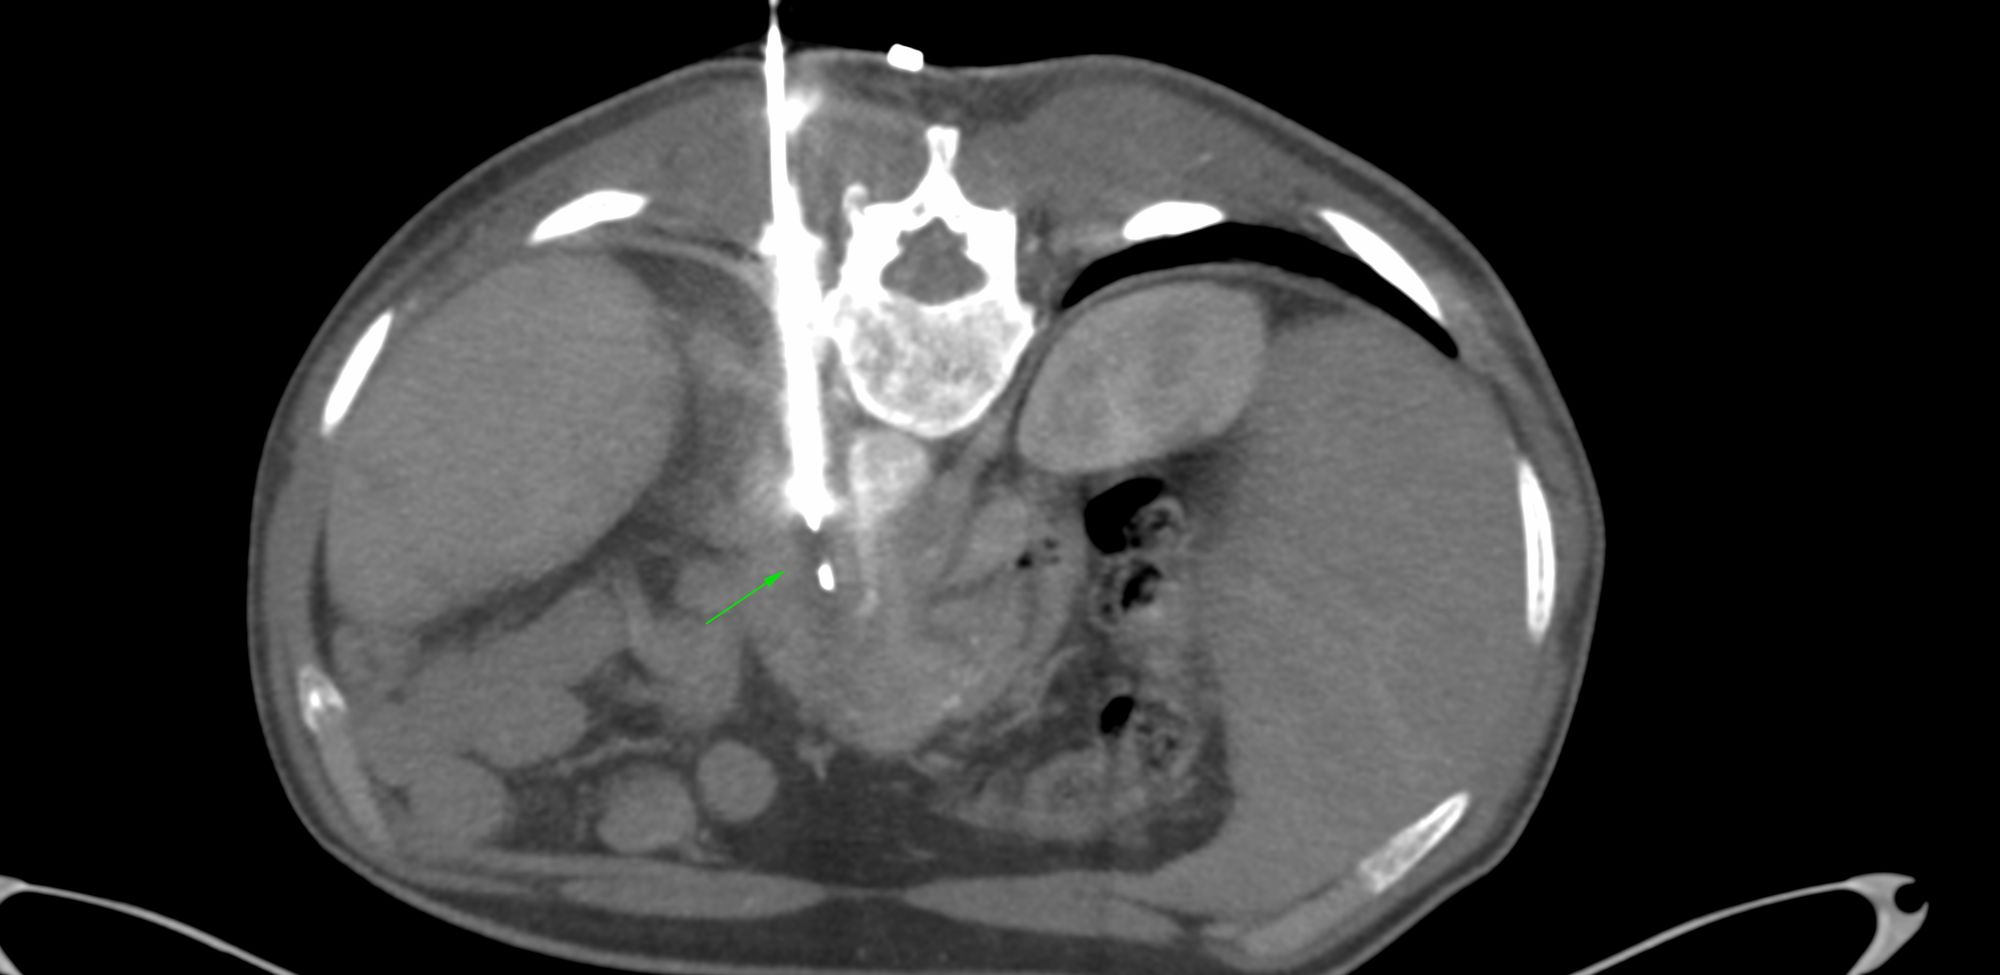

Case 89: Biopsy of Retroperitoneal Fibrosis